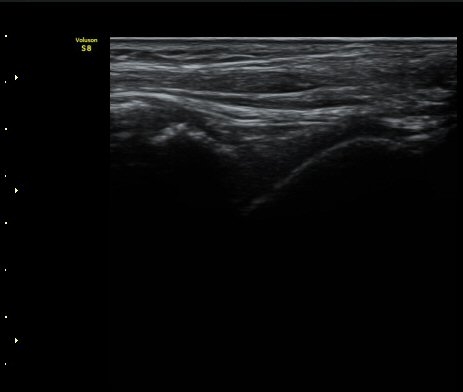

3ÁÖ ÈÄ ÃßÀû°Ë»ç»ó °üÀý³» ºÎÁ¾ÀÌ ¼Ò½ÇµÇ°í(±×¸² 4). Àü°Å°ñºñ°ñÀδëÀÇ Àú¿¡ÄÚ ºÎÁ¾ÀÌ

°¨¼ÒÇÏ°í °ß¿­°ñÀý °ñÆíÀº ºñ°ñ °¡±îÀÌ À§Ä¡Çϰí ÀÖ´Ù(±×¸² 5, 6).

ÃÊÀ½ÆÄ Åõ½ÃÇÏ ºÎÇϰ˻翡¼­ ºñ°ñ°ú ÀδëºÎÂøºÎ¿Í  ºñ°ñ°ú °Å°ñ»çÀ̰¡ ¹ú¾îÁöÁö ¾Ê´Â´Ù

(樨毢 2).